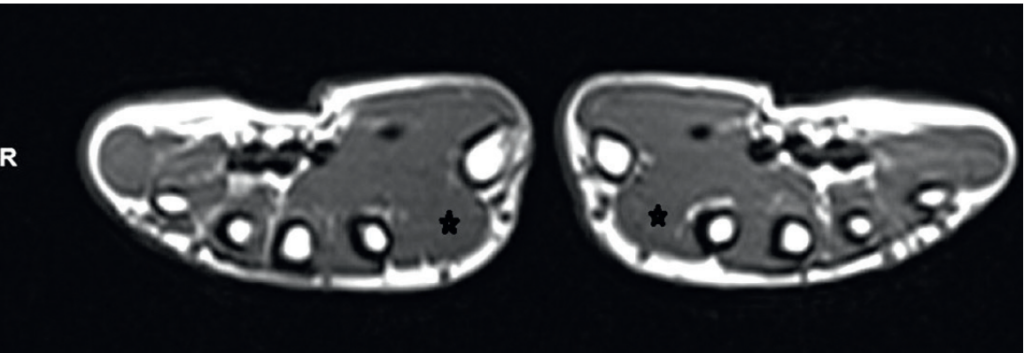

КЛИНИЧЕСКИЙ СЛУЧАЙ

РИС. 1. МРТ обеих рук (Т1-взвешенный аксиальный срез). Первые тыльные межпальцевые мышцы (ТТМ) показа - ны звездочкой. Видно небольшое укрупнение с правой стороны.